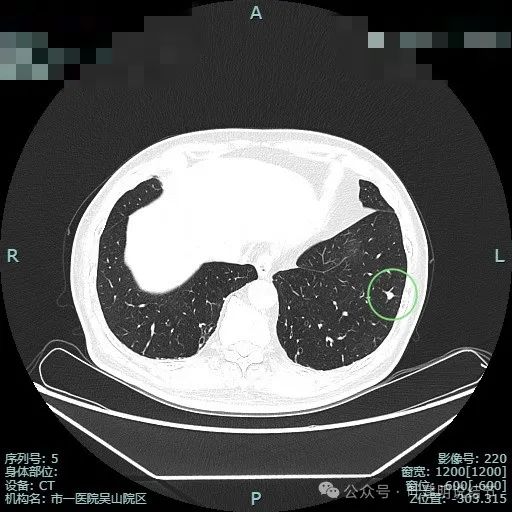

右上叶脊柱旁微小磨玻璃结节,轮廓较清。

右上结节虽小,但轮廓较清,邻近有小血管走行,两者之间有缝隙,说明不太像肺内淋巴结或普通急性炎症。

其实密度不太纯,边缘显毛糙,离叶间裂近,但叶间裂无明显牵拉。

中间似有血管穿行,离胸膜也近的,整体轮廓较清。

此灶考虑肿瘤范畴的可能性大,微浸润性腺癌或不典型增生可能性大,有时细支气管腺瘤也会类似表现。总体可先随访,反正它也不是主病灶。